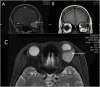

Case presentation: A 43-year-old woman who had a history of small intestinal stromal tumor 4 years ago suffered GIST metastasis to the left orbit. MRI confirmed the presence of a lacrimal gland lesion with isointense on T1 and hyperintense on T2 weighted images. Histopathology analysis of the tumor showed predominantly spindle or oval cells with nuclear pleomorphism and increased mitoses. The tumor also stained positive for c-KIT (CD117) upon immunochemistry, confirming the diagnosis V体育安卓版. .

Conclusions: GISTs typically occur as sporadic solitary tumors, and their common metastasis sites are the liver and the surface of the peritoneum. Orbital involvement is extremely rare. The orbital GIST metastatic tumor has special imaging properties, as evidenced by histopathology, immunochemistry, and magnetic resonance imaging (MRI). V体育ios版.